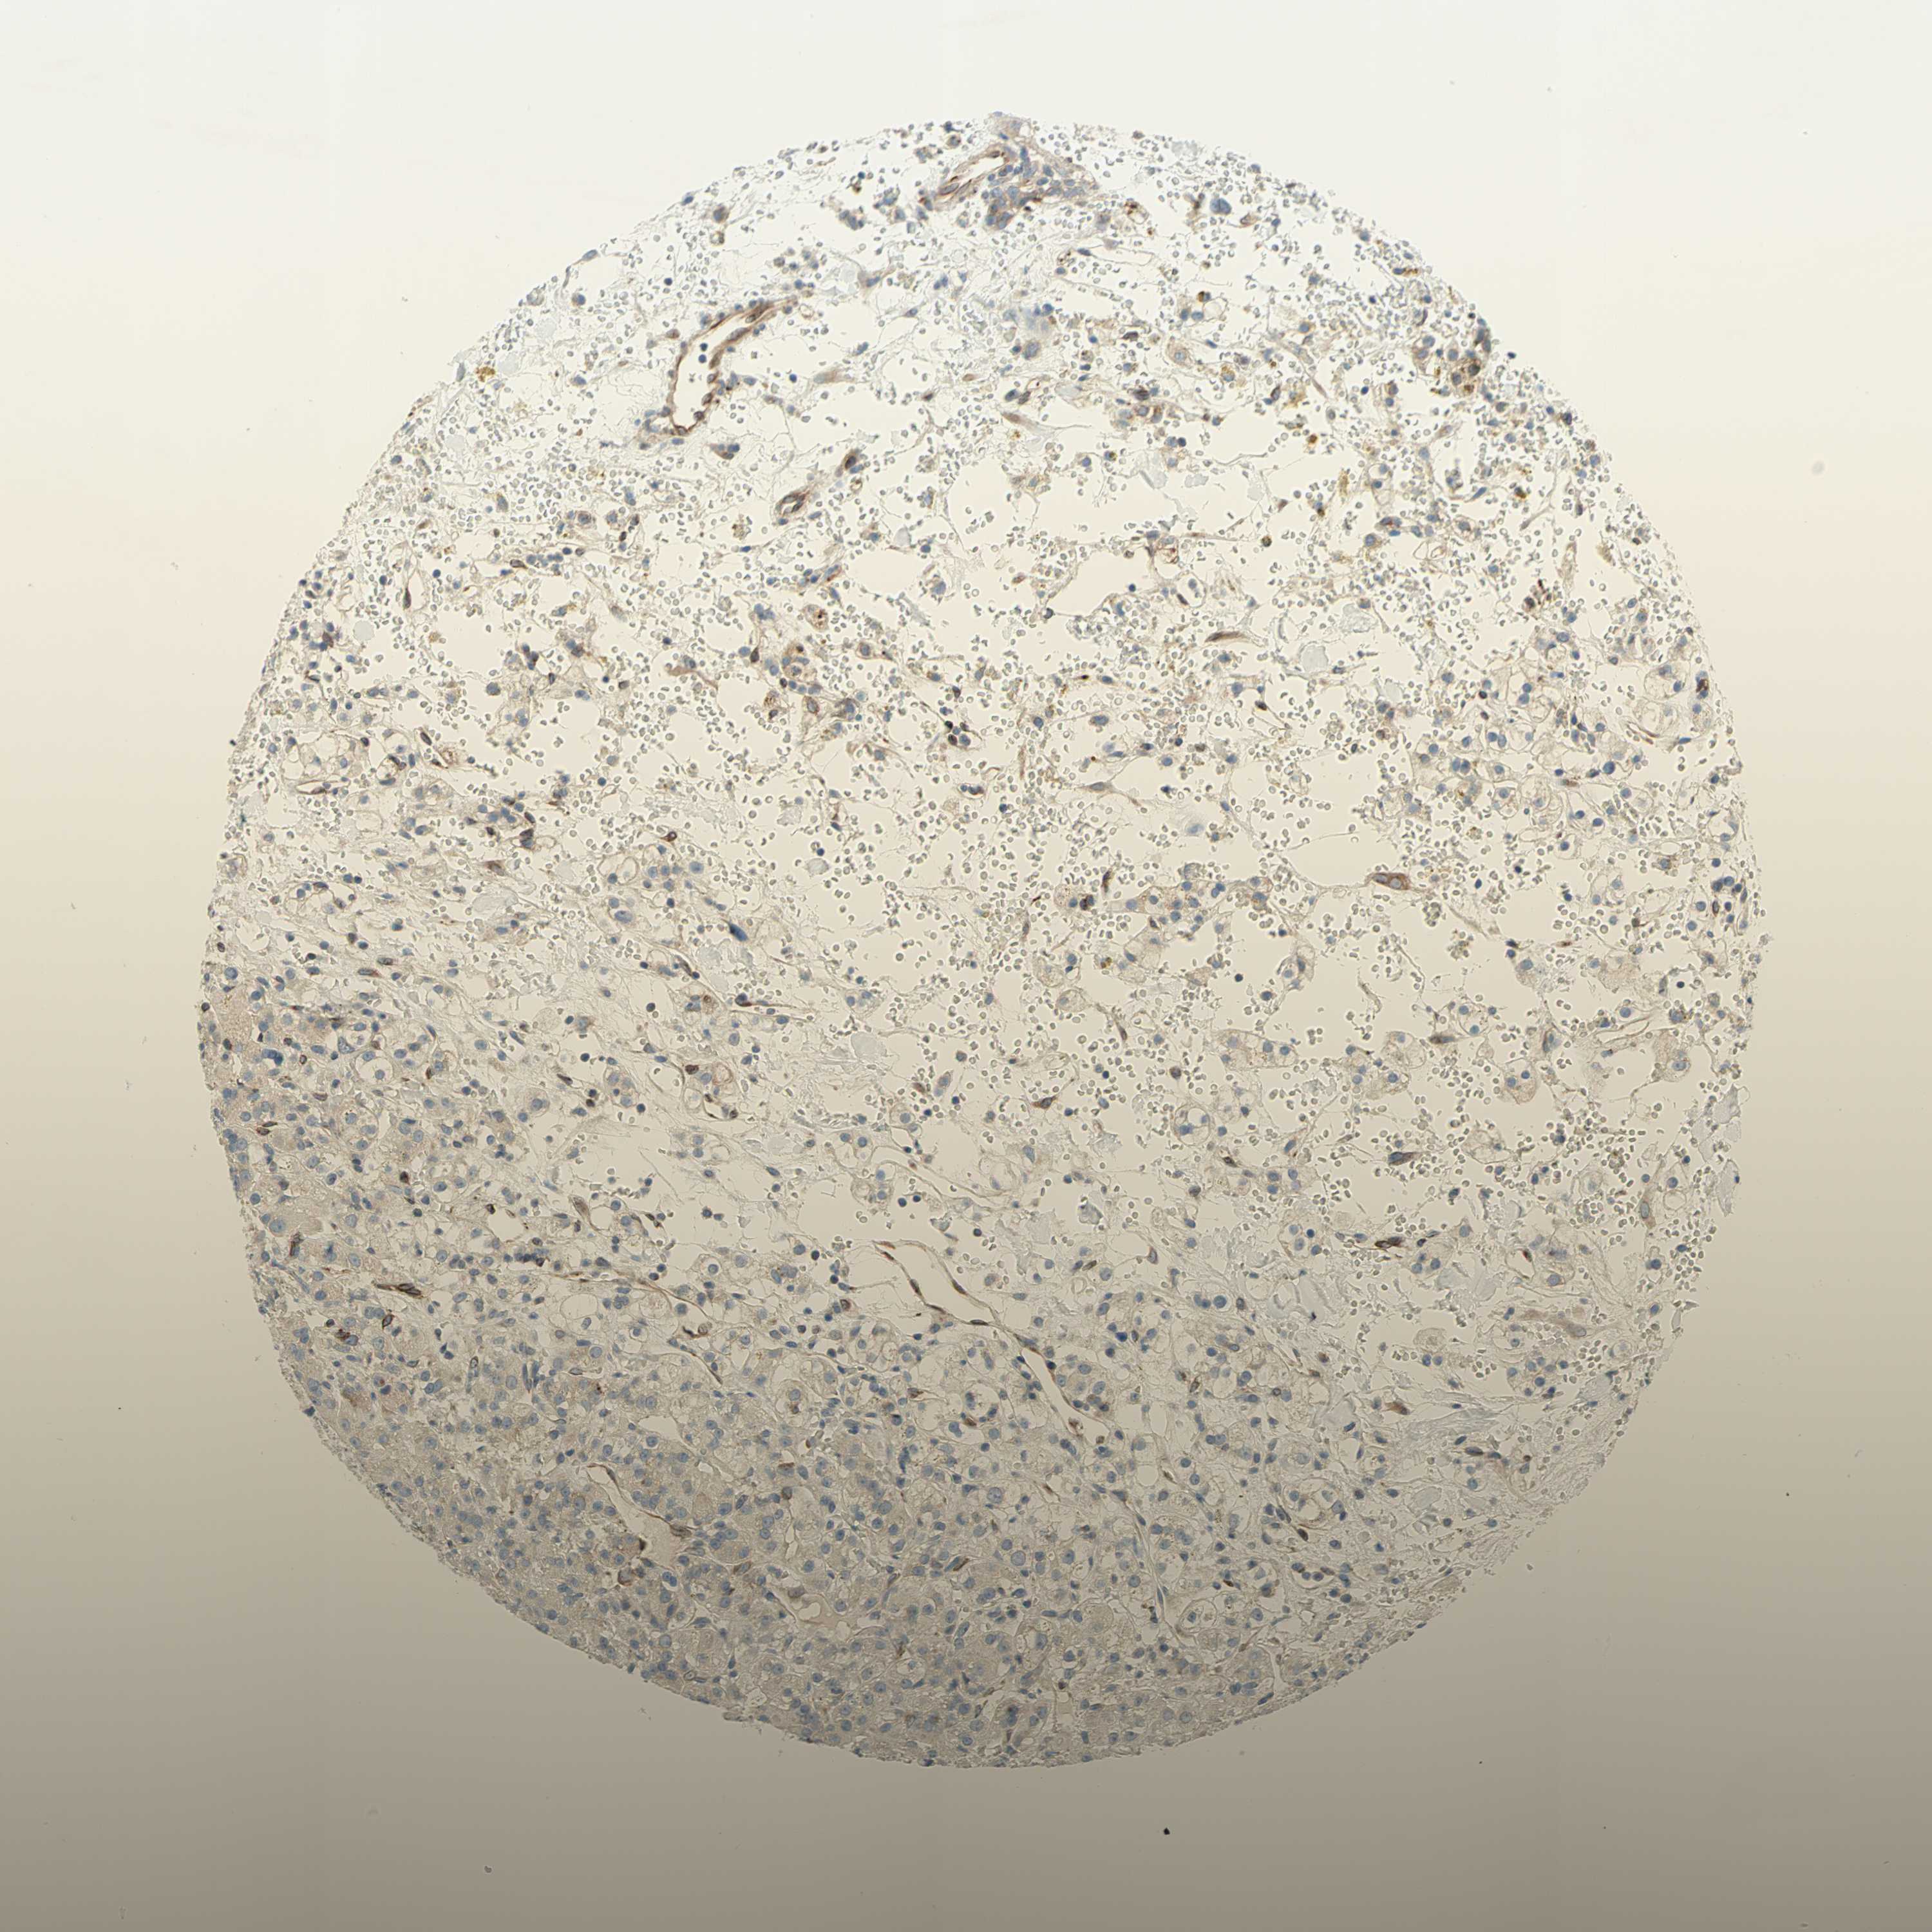

KIDNEY RENAL PAPILLARY CELL CARCINOMA (TCGA) - Interactive survival scatter ploti

The Survival Scatter plot shows the clinical status (i.e. dead or alive) for all individuals in the patient cohort, based on the same data that underlies the corresponding Kaplan-Meier plots. Patients that are alive at last time for follow-up are shown in blue and patients who have died during the study are shown in red.

The x-axis shows the expression levels (FPKM) of the investigated gene in the tumor tissue at the time of diagnosis. The y-axis shows the follow-up time after diagnosis (years). Both axes are complimented with kernel density curves demonstrating the data density over the axes. The top density plot shows the expression levels (FPKM) distribution among dead (red) and alive patients (blue). The right density plot shows the data density of the survived years of dead patients with high and low expression levels respectively, stratified using the cutoff indicated by the vertical dashed line through the Survival Scatter plot. This cutoff is automatically defined based on the FPKM cutoff that minimizes the p-score. The cutoff can be changed by dragging the vertical line or by entering a cutoff value in the square labeled "Current cut-off".

Under the Survival Scatter plot the p-score landscape (black curve; left axis) is shown together with dead median separation (red curve; right axis). Dead median separation is the difference in median mRNA expression between patients who have died with high and low expression, respectively. It is calculated as follows: median FPKM expression of dead patients with high expression - median FPKM expression of dead patients with low expression. This is intended to aid the user in visually exploring custom cutoffs and the associated p-scores and dead median separation.

Individual patient data is displayed and can be filtered by clicking on one or more of the category buttons on the top of the page. Categories describing expression level and patient information include: high, low, alive, dead, female, male and tumor stages. The scale of the x-axis can be toggled between linear and log-scale by clicking on the "x log" button. Mouse-over function shows TCGA ID, patient information and mRNA expression (FPKM) for each patient.

& Survival analysisi

Kaplan-Meier plots summarize results from analysis of correlation between mRNA expression level and patient survival. Patients were divided based on level of expression into one of the two groups "low" (under cut off) or "high" (over cut off). X-axis shows time for survival (years) and y-axis shows the probability of survival, where 1.0 corresponds to 100 percent.

TRAF2 is not prognostic in Kidney Renal Papillary Cell Carcinoma (TCGA)